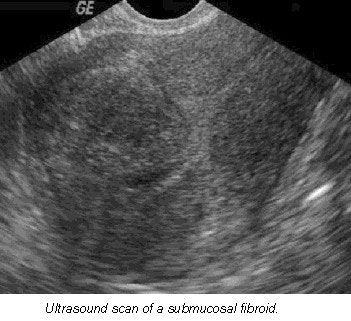

Making an accurate diagnosis of fibroids is extremely important because there are many ways of treating them. Thirty percent of women with fibroids have bleeding, particularly when the fibroids are submucosal in location.

- Women with menorrhagia, increased volume or duration of bleeding, are far more likely to have adenomyosis than fibroids. Ultrasound features for fibroids include one or more discrete masses with a hypoechoic halo (compressed myometrium), diffuse posterior shadowing, and calcification in late stages or after pregnancy. However, cysts are uncommon.

- Fibroids can be hypoechoic, isoechoic (same echogenicity as myometrium), or hyperechoic. In comparison, the characteristics of adenomyosis include ill-defined regions of mixed textural changes, asymmetric myometrial thickening, streaky shadowing posteriorly, and no calcifications.